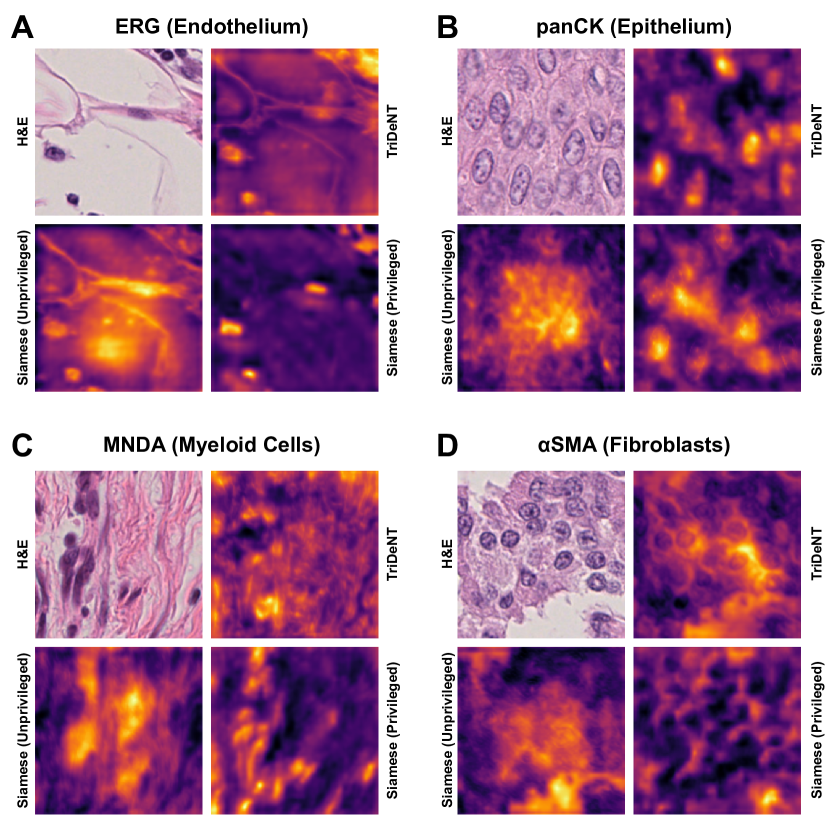

We also analyse the activation maps for each model using GradCAM as described in section S3. This offers more insight into the areas of the image which are contributing most heavily to the models’ representations. In Figure 4(b) we present some representative examples, however, a larger selection which was chosen at random is presented in Figures S10 to S25. The larger selection makes it easier to see the emergent patterns, including that privileged Siamese models tend to mainly identify features which are strongly present in both inputs, while unprivileged Siamese models tend to learn more diffuse features that are not specific to one cell phenotype or image region. TriDeNT ♆ incorporates both sets of features, learning both features specific to the privileged data and more the general features associated with unprivileged Siamese networks.

We can see in Figure 4(b) panel A that for ERG, the privileged Siamese model focuses almost exclusively on any nuclei which could be endothelial cells. As there are very few endothelial cells in the dataset, it could be an effective strategy to identify anything that could potentially be an endothelial cell to minimise the difference between the representations of the H&E model and the IF mask model. In the corresponding unprivileged Siamese image, we see that the model identifies some of these nuclei, albeit less strongly, but also focuses heavily on the other tissue and even the background, while strongly fixating on two spots of debris in the center of the image. This model has less ‘incentive’ to learn the weak features related to endothelial cells as these occur rarely and are not easy to detect, while more generic strong features such as the presence of connective tissue and the prevalence of background are more common and predictable from augmented images. We see that TriDeNT ♆ combines these two feature sets, strongly identifying nuclei while also identifying the connective tissue.

In panel C we see a similar pattern, with the privileged Siamese model fixating solely on the nuclei, while the TriDeNT ♆ model takes a more balanced approach. The unprivileged Siamese model appears to focus on a single cluster of nuclei while neglecting others, and similarly identifies an area of fibroblasts with its distinctive pattern but does not others.

In contrast to panels A and C which represent models with poor privileged Siamese results, panels B and D represent models whose privileged Siamese results were comparable to both TriDeNT ♆ and even the supervised baseline. It is therefore interesting to note that there are far more similarities between the privileged Siamese and TriDeNT ♆ models in both cases. Particularly in panel B, TriDeNT ♆ and the privileged Siamese model return virtually identical heatmaps, with both strongly identifying epithelial nuclei and neglecting the same areas of connective tissue. The unprivileged model in this case appears to focus solely on the centre of the image, giving a significantly different heatmap to the other panels.

Panel D again shows the previous pattern, with the privileged Siamese model identifying the features strongly present in the privileged data – fibroblasts – while neglecting the nuclei present. TriDeNT ♆ also strongly identifies the connective tissue, but, unlike the privileged Siamese model, does not completely neglect the nuclei. The unprivileged Siamese model primarily identifies background, and does not appear to identify the nuclei in this example.